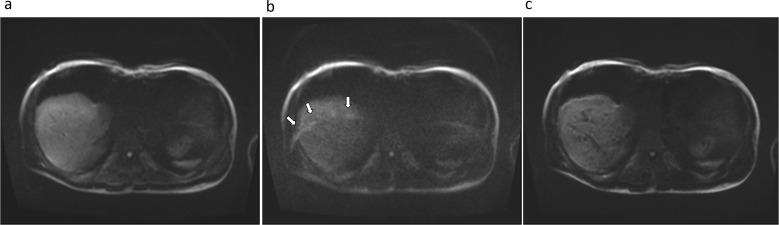

Purpose: Although diffusion-weighted imaging (DWI) with ultra-high b-values is reported to be advantageous in the detection of some tumors, its applicability is not yet known in biliary malignancy. Therefore, this study aimed to evaluate the impact of measured b = 1400 s/mm2 (M1400) and calculated b = 1400 s/mm2 (C1400) DWI on image quality and quality of lesion discernibility using a modern 3T MR system compared to conventional b = 800 s/mm2 DWI (M800).

Methods: We evaluated 56 patients who had pathologically proven biliary malignancy. All the patients underwent preoperative or baseline 3T MRI using DWI (b = 50, 400, 800, and 1400 s/mm2). The calculated DWI was obtained using a conventional DWI set (b = 50, 400, and 800). The tumor-to-bile contrast ratio (CR) and tumor SNR were compared between the different DWI images. Likert scores were given on a 5-point scale to assess the overall image quality, overall artifacts, ghost artifacts, misregistration artifacts, margin sharpness, and lesion discernibility. Repeated-measures analysis of variance with post hoc analyses was used for statistical evaluations.

Results: The CR of the tumor-to-bile was significantly higher in both M1400 and C1400 than in M800 (Pa < 0.01). SNRs were significantly higher in M800, followed by C1400 and M1400 (Pa < 0.01). Lesion discernibility was significantly improved for M1400, followed by C1400 and M800 for both readers (Pa < 0.01).

Conclusion: Using a 3T MRI, both measured and calculated DWI with an ultra-high b-value offer superior lesion discernibility for biliary malignancy compared to the conventional DWI.